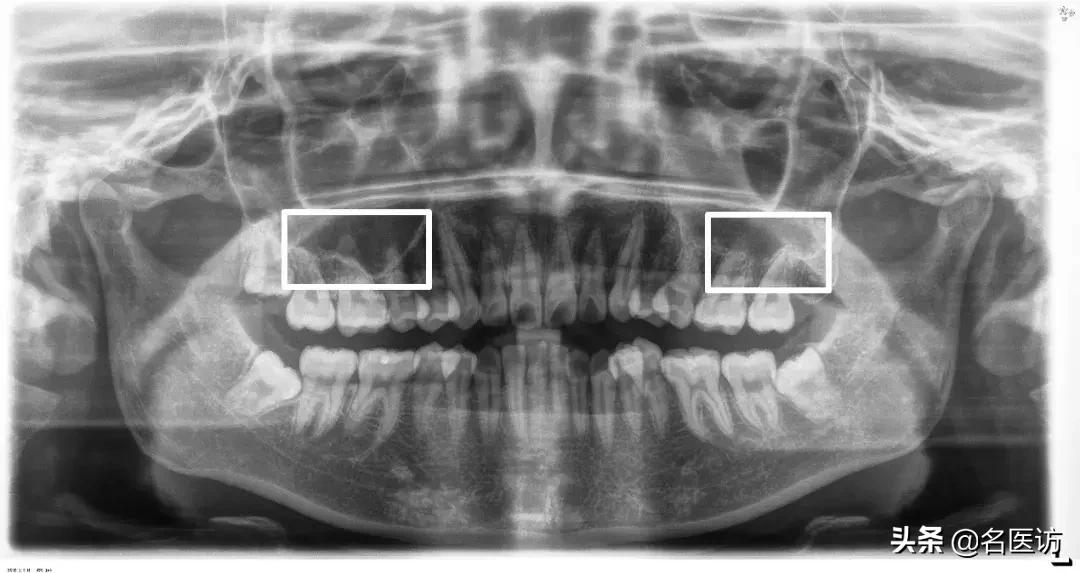

3、颞下颌关节

除了美观外,功能健康也是很多人选择矫正的主要原因,因此在矫正前后查看关节的情况很重要。

髁突磨损

全景片观察的主要是颞下颌关节的对称性和髁突的形态,如果关节严重不对称或髁突有明显磨损,需要去做进一步的详细检查,不能贸然开始做矫正。